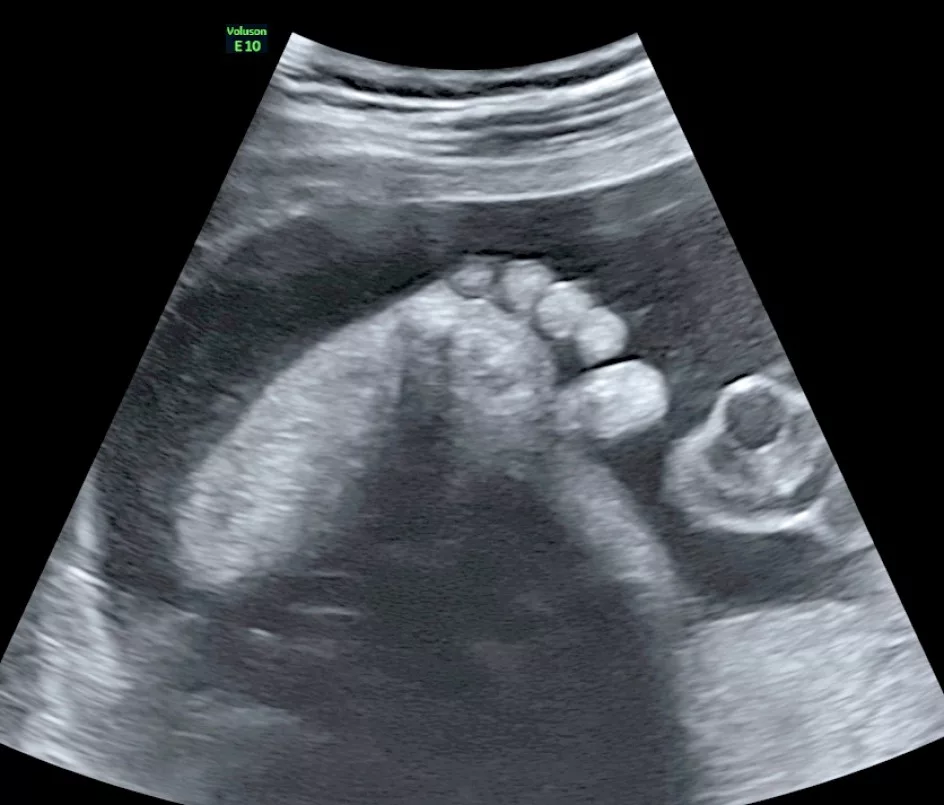

• les extrémités des membres (en particulier doigts et orteils),

• L’étude de la morphologie du fœtus, c’est-à-dire sa forme extérieure et différents organes internes. Le placenta, le cordon ombilical et le liquide amniotique seront également examinés.